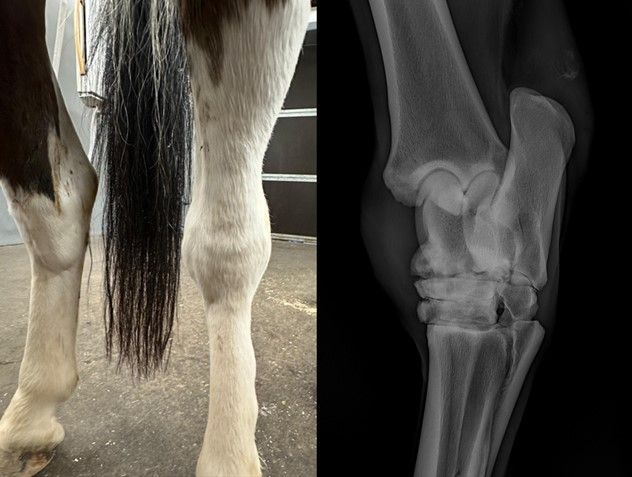

Bij een klinische keuring wordt de algehele gezondheid van het paard uitgebreid onderzocht. We beoordelen o.a. hart, longen, ogen, gebit, voedingstoestand, beenwerk en hals/rug/bekken.

Ook afwijkende bultjes, castratielittekens, coördinatieproblemen en overige afwijkingen worden in kaart gebracht.

Met een röntgenologische keuring brengen we het skelet in beeld. Hiermee verkrijgen we een overzicht van eventuele OC(D), cystes, artrose, kissing spines, et cetera. Dankzij extra zware kwaliteit röntgenapparatuur, kunnen ook goede foto's van hals en rug worden genomen.